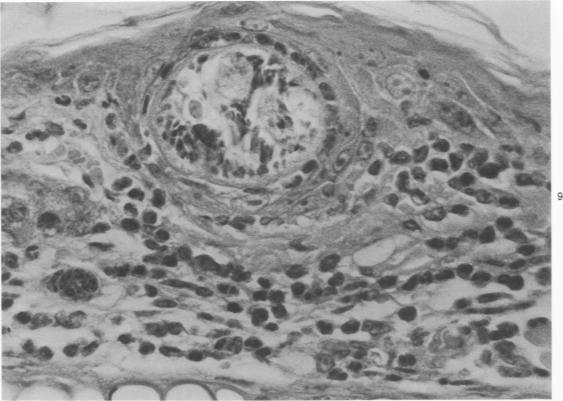

Exposure of the mouse skin to Schistosoma mansoni cercariae gives rise to acute, exudative inflammation in both normal and immune mice, but the immune response is anamnestically accelerated and is oesinophil-enriched, thereby enhancing opportunities for tegumental contact of schistosomula with host leukocytes, particularly with eosinophils. Many of the inflammatory changes occurring within the first 48 hours after exposure are due to cercarial products, e.g., "penetration tracts," but some remain demonstrable when schistosomula metamorphosed in vitro are injected intradermally and are therefore directed against the schistosomula themselves, such as the leukocyte "streaming patterns" seen in their pathways. In contrast to earlier observations in primates, cellular responses to schistosomula in the mouse lung 4 days after penetration are minimal in either normal or immune mice. Thus, immune cellular responses to schistosomula in mice are limited to an early time period after cercarial penetration and are morphologically suggestive of an antibody-mediated response rather than of delayed hypersensitivity. Our observations complement earlier evidence suggesting that antibody-mediated host leukocyte contact with schistosomula initiates the killing of challenge parasites in immune mice, with the eosinophil probably playing a crucial role.

将曼氏血吸虫尾蚴暴露于小鼠皮肤会在正常小鼠和免疫小鼠中引发急性渗出性炎症,但免疫反应会呈回忆性加速且富含嗜酸性粒细胞,从而增加了童虫与宿主白细胞(特别是嗜酸性粒细胞)体表接触的机会。暴露后最初48小时内发生的许多炎症变化是由尾蚴产物引起的,例如“侵入道”,但当在体外变态的童虫皮内注射时,一些变化仍然明显,因此是针对童虫本身的,比如在其路径中看到的白细胞“流动模式”。与早期在灵长类动物中的观察结果相反,在正常或免疫小鼠中,穿透后4天小鼠肺内对童虫的细胞反应都很轻微。因此,小鼠对童虫的免疫细胞反应仅限于尾蚴穿透后的早期阶段,并且在形态学上提示是一种抗体介导的反应而非迟发型超敏反应。我们的观察结果补充了早期证据,表明抗体介导的宿主白细胞与童虫的接触启动了免疫小鼠中对攻击寄生虫的杀伤,嗜酸性粒细胞可能起着关键作用。